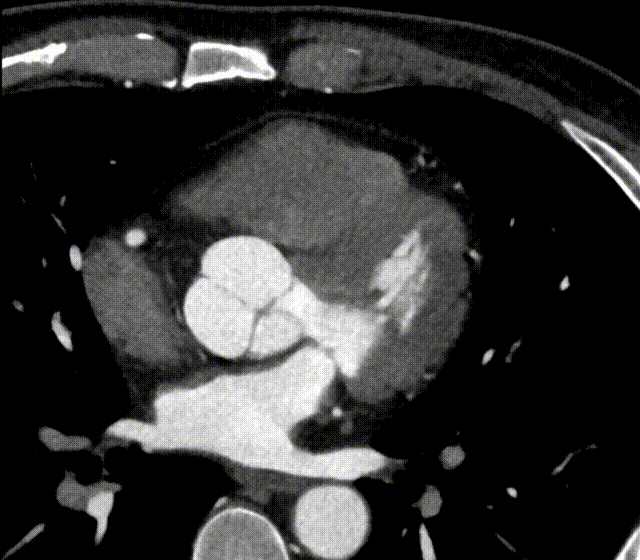

恍惚之间,是否只觉此为MRI?

上述二图,皆出自同一人、同一种、同一次检查图像,乃冠脉CTA图像

传统CT通常只能提供单时相静态结构成像,但uCT SiriuX打破了局限,可提供全心动周期多个时相的清晰结构成像信息,动态展示心脏结构运动变化,达到了类DSA、类MR的效果。

uCT SiriuX落地临床验证中,我们切身体会了这款设备的全脏器覆盖能谱成像功能,可在单心动周期内完成全心能谱采集,提供多种能谱图像类型。

例如,虚拟单能图像可优化冠脉图像对比度,有效消除血管管腔中钙化导致的晕状伪影,确保准确的血管评估;同时,基于能谱图像的物质识别技术,还可进行斑块成分分析,进一步提升诊断精度。